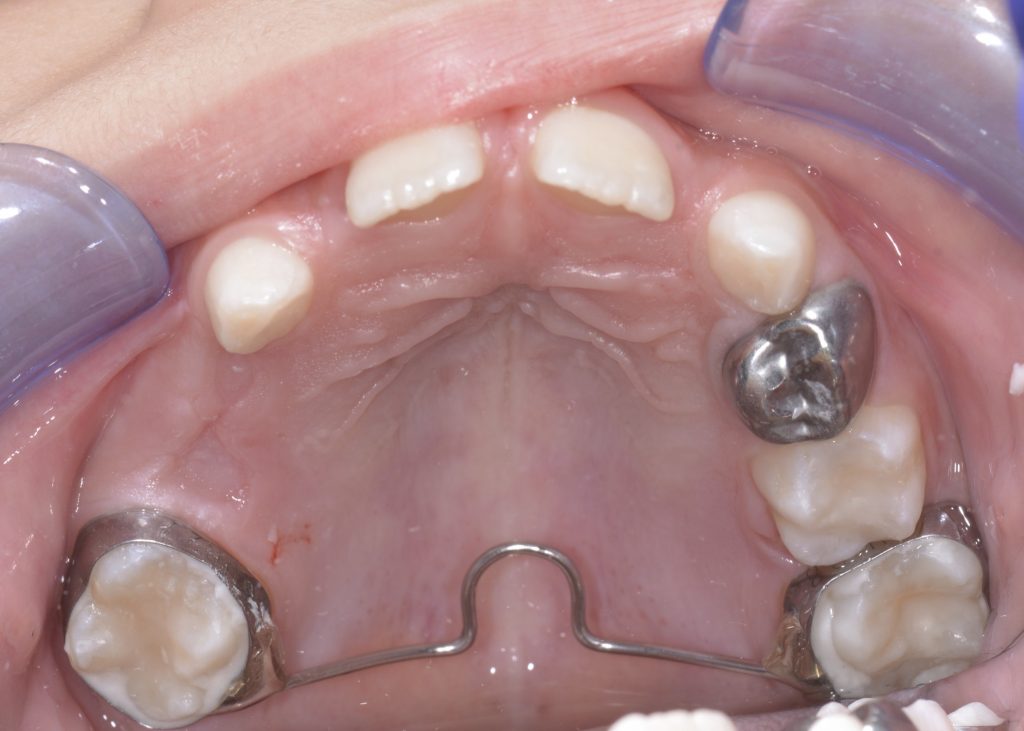

Removing A Space Maintainer . Space loss typically occurs more rapidly in the maxilla than in the mandible. — the safest way to prevent future malocclusions from tooth loss is to place a space maintainer that is effective. — well, placing space maintainers is a delicate process that only dental professionals can perform. a dental space maintainer should be removed when the permanent tooth is ready to erupt. Your dentist will know when this. Space loss usually occurs within 6 months after premature loss of a primary molar (simon et al., 2012). In essence, the procedure consists of. — space maintainers should be inserted within a few weeks after an extraction. — the royal college of surgeons guidance on the extraction of primary teeth state that space maintainers would be. — the space maintainer can also be used in the case of permanent tooth agenesis when it is not possible to close the space through orthodontic.